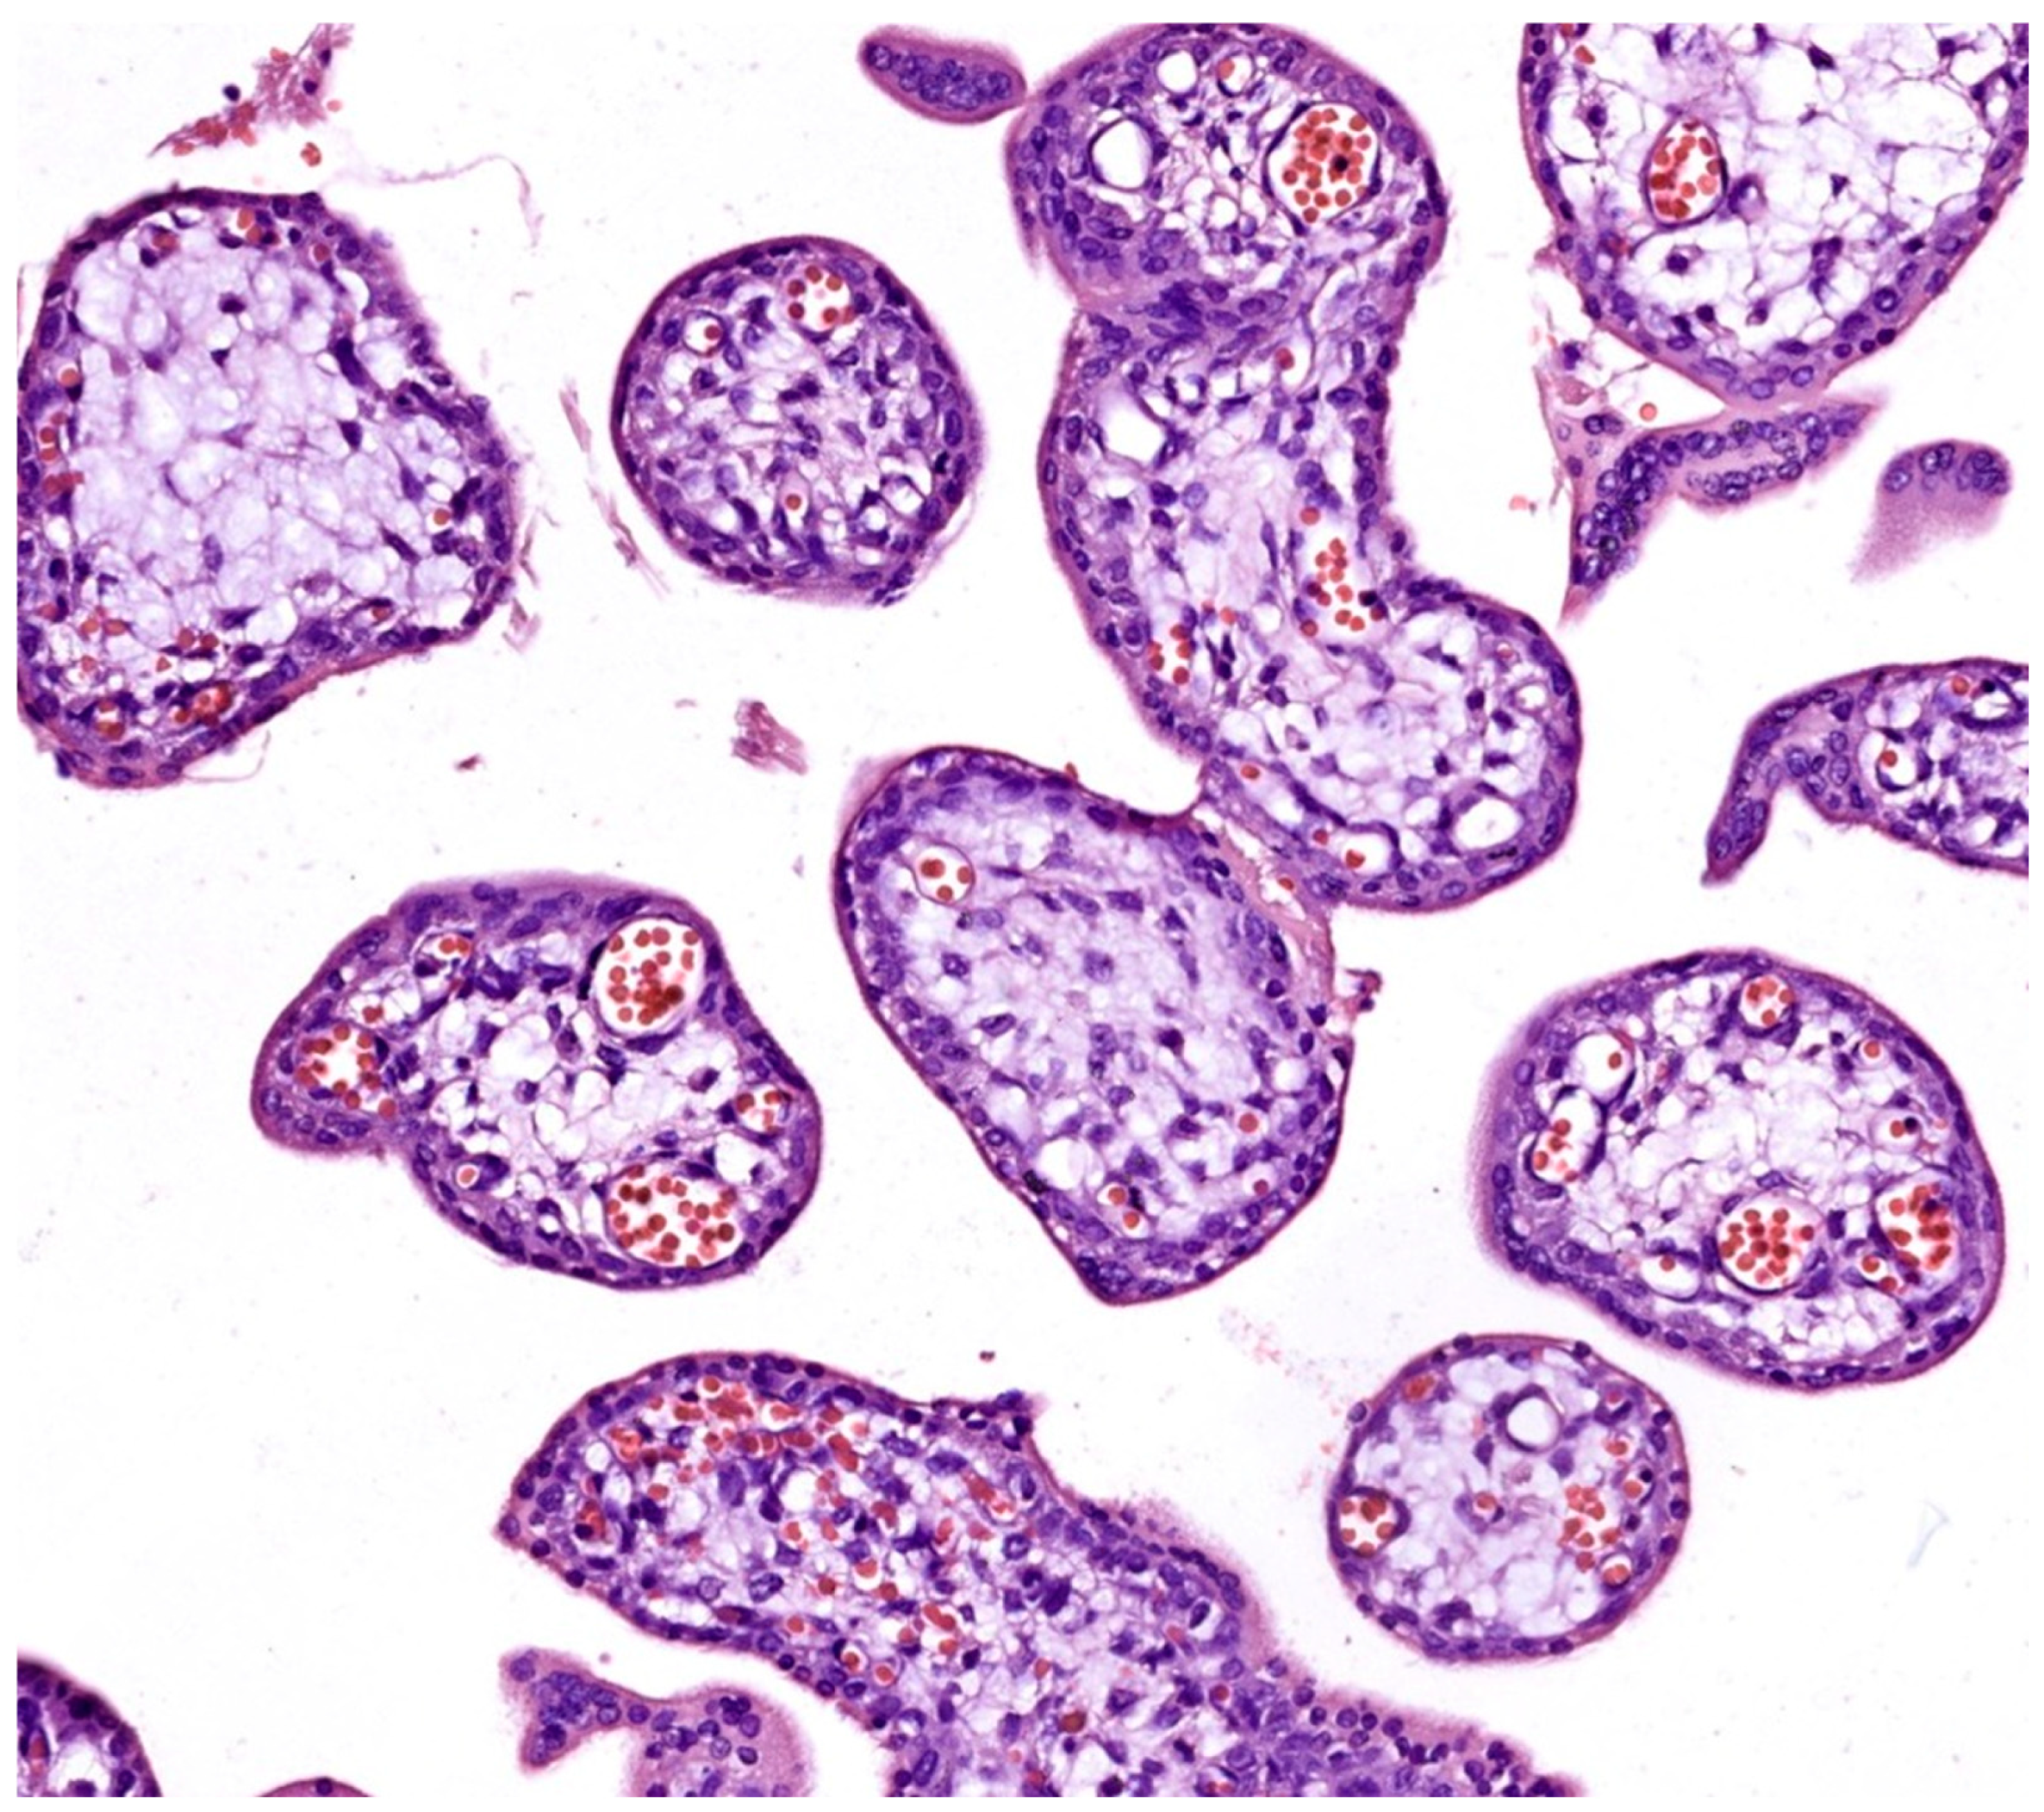

• Chorangiosis and accelerated villous maturation: Seen only in spontaneous abortions (see Figure 2);

• Syncytial knotting: Ranging from sporadic and slightly increased in elective abortions (see Figure 1) to more extensively apparent in spontaneous abortion samples (see Figure 3B,E).